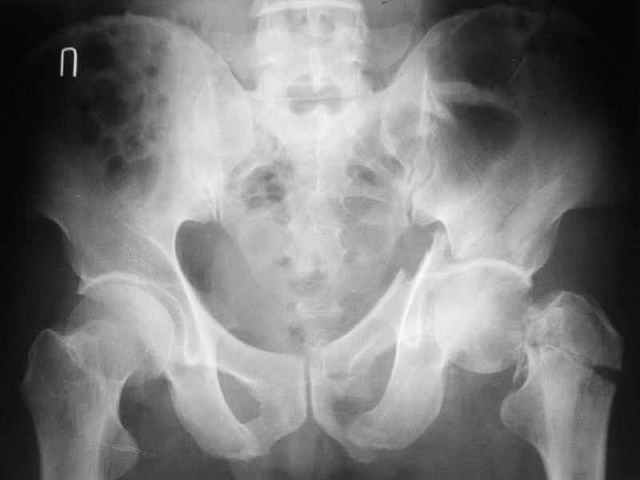

Контрольный снимок перед разрешением нагрузки прямой 13/10/03

Больной 18 мая 2003 года в автоаварии получил перелом левой вертлужной впадины, вывих бедра. Госпитализирован в один из стационаров области.Вывих вправлен. В последствии бедро вывихивалось еще дважды. На консультацию был представлен снимок от 19.05.03г., больной переведен к нам 3.06.03г. Снимок при поступлении - перелом впадины, задне-верхний вывих бедра. 05.06.2003 г. выполнено открытое вправление вывиха левого бедра и остеосинтез стенки вертлужной впадины двумя винтами. Послеоперационный период без осложнений. Объем движений в левом тазобедренном суставе восстановился полностью. Выписан на амбулаторное лечение в удовлетворительном состоянии с рекомендациями 3 месяца ходить на костылях без нагрузки на оперированную конечность. На контрольных рентгенограммах левого тазобедренного сустава 13.10.2003 г. - признаки консолидации перелома; плотность, форма головки и состояние суставных поверхностей удовлетворительные. Разрешена дозированная осевая нагрузка, на конечность с использованием дополнительной опоры. 19.12.2003 г. больной обратился с жалобами на боли в левом тазобедренном суставе. На рентгенограммах левого тазобедренного сустава 19.12.2003 г., 20.02.04г. - асептичекий некроз головки бедра. 5.04.04г. - эндопротез. Сейчас ходит без трости, не хромает. Особенность эндопротезирования - при удалении винтов прослежена линия перелома заднего края впадины и предложено установить чашку несколько меньшего диаметра, чтобы она была покрыта несломанной частью.